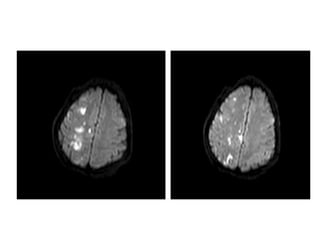

Case 2

• 85 year old male who woke up with left face, arm, and leg

numbness

• History of HTN, DM, and tobacco use

• Meds: Insulin, aspirin

• BP- 168/96, P– 92

• General exam: Unremarkable, RRR

• NEURO EXAM:

- Decreased sensation on left face, arm, and leg

Answer

• Right thalamic lacunar infarct

• Not a candidate for intervention

• Discharged to rehab 72 hours after admission